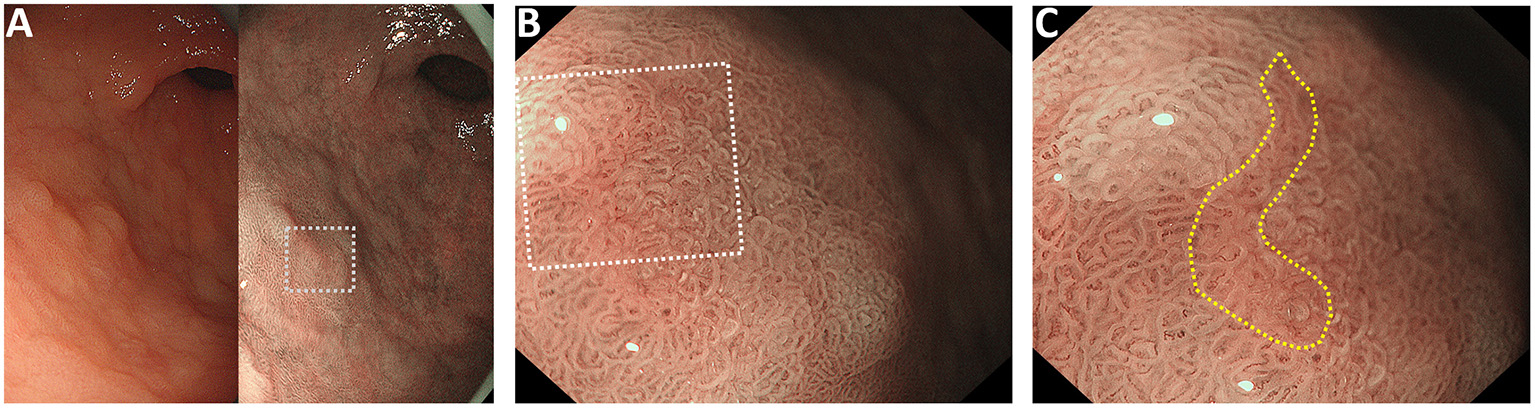

When EGC is observed, the color of the gastric mucosal surface is usually masked by the surface microvessels, so any color changes in the superficial mucosal epithelium are easily missed. We have occasionally observed a pink color change on the superficial mucosal epithelium when suspicious gastric malignant lesions are visualized with ME-NBI, when the DLs of these lesions are either indeterminate or clear (Figure 1, Supplementary Figure 1). The lesions that showed a pink color change, regardless of whether the DL was indeterminate or visible, were confirmed as gastric cancer by histological examination (Figure 2, Supplementary Figure 2). We designated this pink color change in a gastric cancer lesion under ME-NBI the “pink pattern” (the additional images can be seen in Supplementary Figure 3). Interestingly, based on the further observation of histopathological slices, we found that the nucleus-to-cytoplasm ratio of the epithelial cells in these cancerous lesions was higher than that of non-cancerous lesions (Figure 2, Supplementary Figure 2). Therefore, we hypothesized that this pink pattern on ME-NBI images of gastric cancer lesions correlated strongly with the change in the nucleus-to-cytoplasm ratio of the gastric epithelial cells in these lesions on histopathological images.

Figure 1

Representative case of the “pink pattern” when the demarcation line (DL) is indeterminate. (A) Suspected lesion of early cancer in the gastric antrum (dotted boxed area). Left panel shows the conventional white light imaging findings and the right panel shows the narrow-band imaging findings. (B) Magnified image of the dotted boxed area in (A). DL is indeterminate. (C) Magnified image of the dotted boxed area in (B). “Pink pattern” is observed in the lesion (within the yellow dotted line).